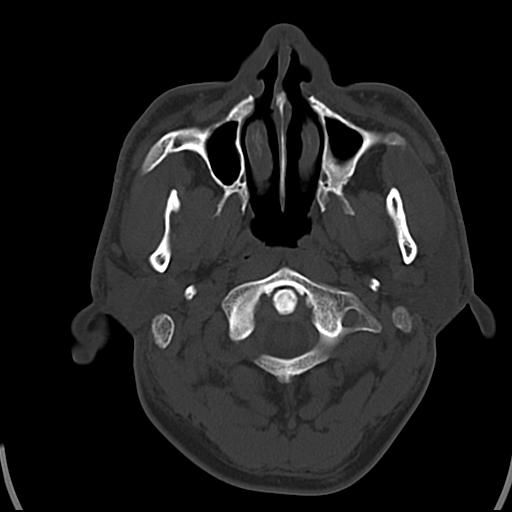

头皮下高密度结节影???临床上在老年男性比较常见。大家看看是什么?成因是? 本例患者,男性,51岁。外伤来诊。无染发史及发根植入史。